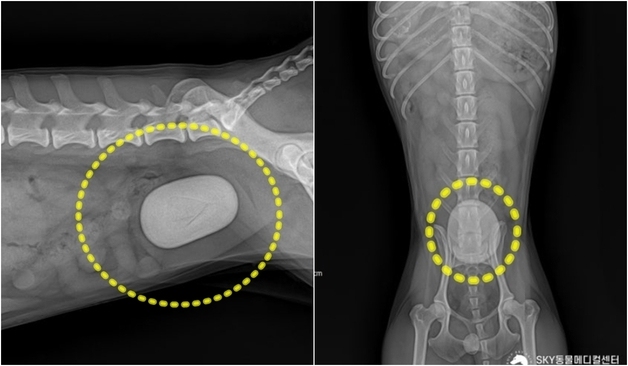

본문 이미지 - SNC동물메디컬센터 최중연 대표원장이 최근 병원 공식 유튜브 채널 'NEVEROFF(네버오프)' 인터뷰를 통해 수의사가 된 이유와 직업에 대한 생각을 담담하게 전했다(유튜브 채널 NEVEROFF 갈무리). ⓒ 뉴스1

SNC동물메디컬센터 최중연 대표원장이 최근 병원 공식 유튜브 채널 'NEVEROFF(네버오프)' 인터뷰를 통해 수의사가 된 이유와 직업에 대한 생각을 담담하게 전했다(유튜브 채널 NEVEROFF 갈무리). ⓒ 뉴스1